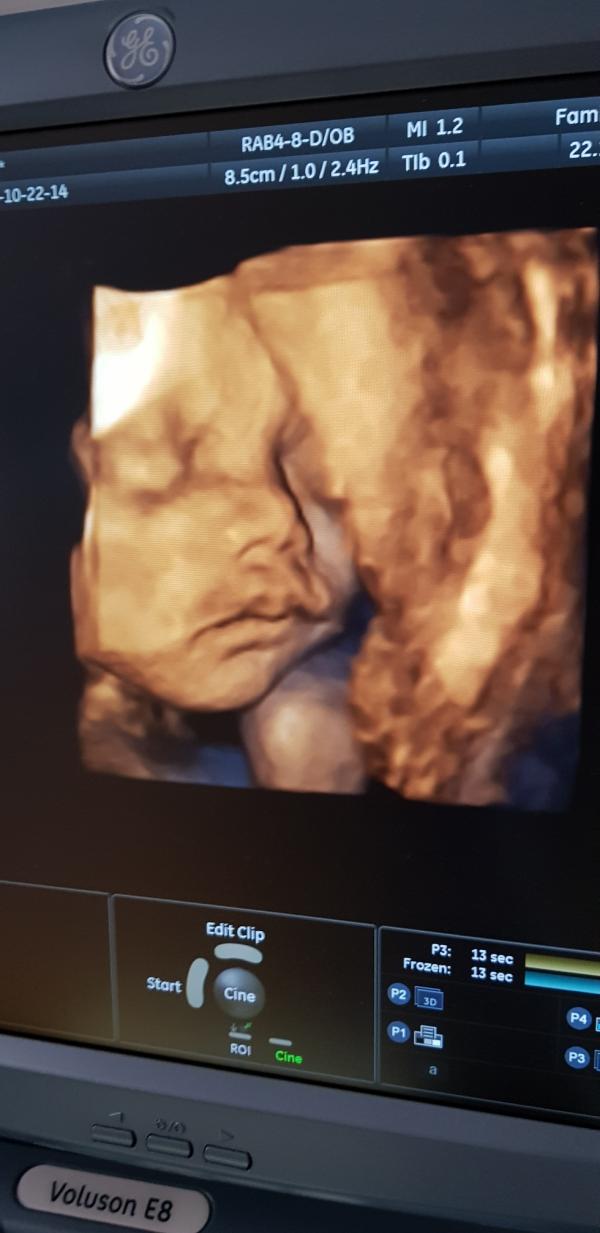

Всем 🖐! Была вчера на узи и оказывается моя малышка до сих пор на попке сидит🤔видимо ей так удобно и обвитие однократное есть, это наверное из за того что я вяжу (ну как не вязать, когда розовые пряжи 5лет пролежали в сундуке и наконец то пришло их время выйти на свет😊) и вес 1.330кг (показался маленьким тоже)но остальное все нормально, теперь хотела спросить: разрешают ли рожать самой если ребенок лежит в тазовом предлежании??? Все таки хочется родить самой (ее здоровье важнее конечно, надеюсь моя малышка повернется к тому времени), близнецов попками и родила, но это в Астане, а как вот у нас в Атырау, незнаю, надеюсь на лучшее🙌🤗